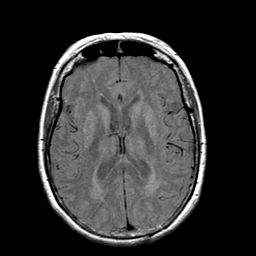

Stroke: proton density-weighted MR #1 -- Slice #14

[Home][Help][Clinical] Slice 14